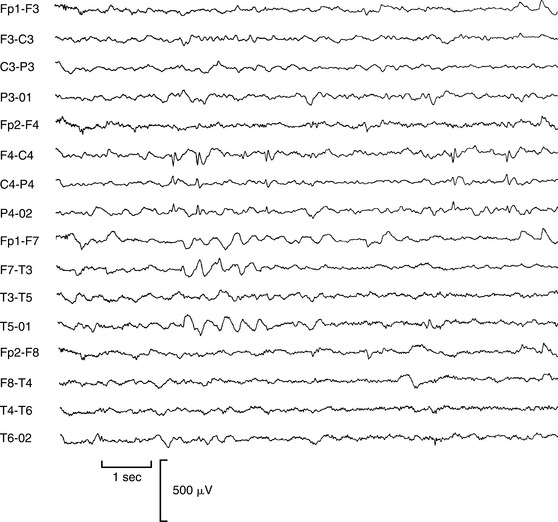

Complex partial seizures of frontal lobe origin are atypical and often differ dramatically from seizures originating in the temporal lobe. Although there are many variations, frontal lobe complex partial seizures tend to begin and end abruptly; have few, if any, postictal symptoms; and involve often bizarre motor manifestations, such as asynchronous thrashing or flailing of arms and legs, pelvic thrusting, pedaling leg movements, and loud vocalizations that may appear as psychiatric disorders.19 Fig. 36-6 presents the EEG of a woman with complex partial seizures, showing focal spike discharges in the right central region.